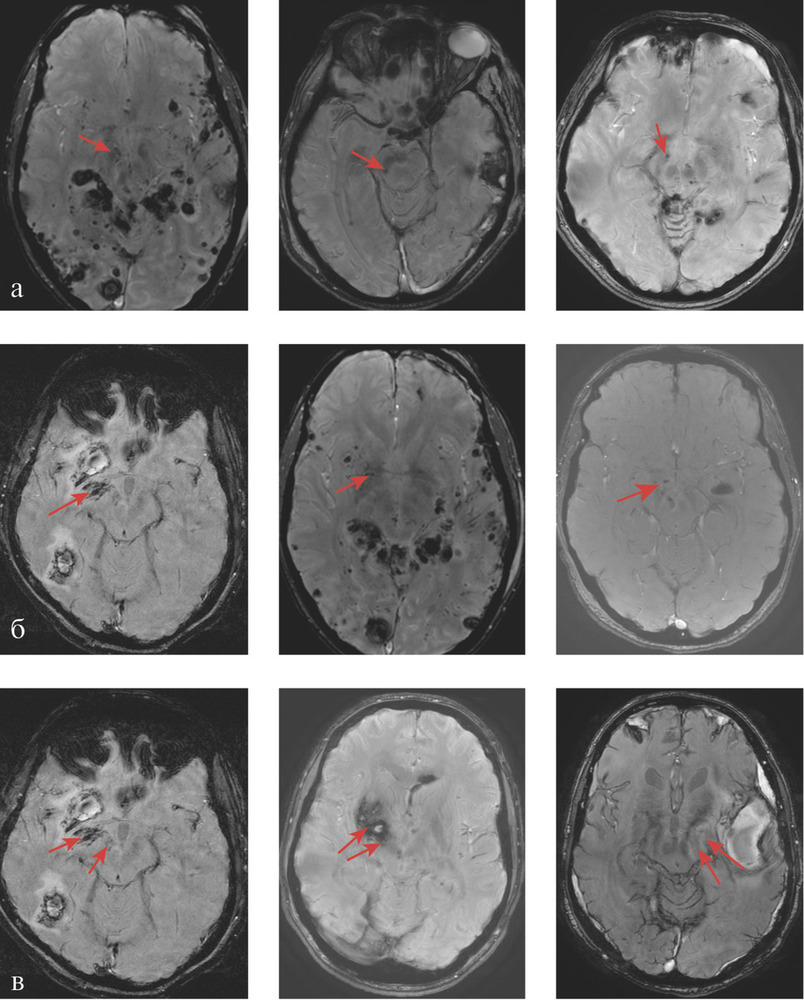

Методы нейровизуализации. МРТ головного мозга проводилось на 3 Т томографе GE в стандартных режимах (T1, T2, FLAIR) и режимах SWI/Т2* GRE, DWI, что позволило оценить как ишемические, так и мелкие геморрагические очаговые повреждения. У каждого пациента, по данным МРТ, было оценено повреждение отдельных подкорковых структур и зон ствола головного мозга, являющихся проекциями основных нейромедиаторных систем мозга (рис. 1),

а также области поражения лобных долей (медиобазальные, полюсные и дорзолатеральные отделы). Статистические методы. Обработка данных проведена в пакете программ Statistica 8.0. («StatSoft Inc», США). Во всех случаях для статистической оценки были использованы непараметрические критерии. Для анализа качественных признаков применялся критерий Фишера (F), для оценки влияния анатомических факторов на риск развития нестабильной гемодинамики рассчитывались отношения шансов, чувствительность и специфичность каждого фактора. Результаты считались статистически значимыми при р<0,05.

Таким образом, анализ показал, что нарушение ауторегуляции мозгового кровотока у пациентов с ДАП головного мозга часто ассоциировано с наличием первичного повреждения черной субстанции, области ядра Мейнерта и их сочетанием (рис. 2).